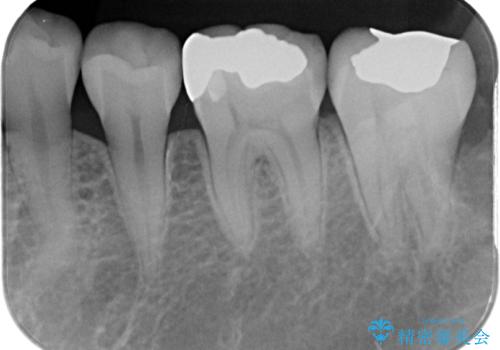

- 当院で矯正後に銀歯が目立つのでやり替えたいと来院された患者様です。銀色の詰め物(メタルインレー)と歯の間に隙間を認め、あまり歯を削りたくないとのことで、患者様と相談の結果セラミックインレーでの治療を行うことになりました。

拡大鏡視野下で、銀色の詰め物(メタルインレー)、保険のプラスチック、虫歯の除去を行い、セラミックインレーに適した形に整えました。